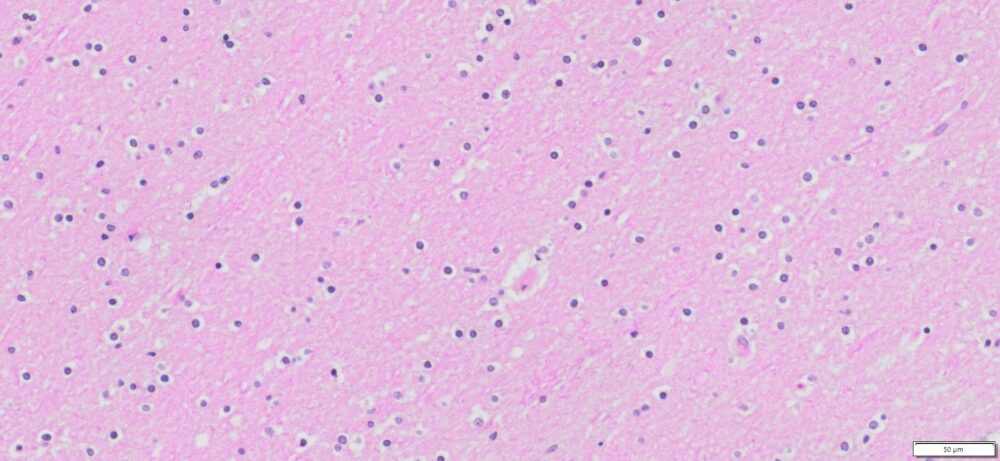

| HuPS-09002A | Brain | Normal Human Cerebral Gray and White Matter | Male/44 | NA |

Human tissue was fixed in formalin immediately after excision and embedded in paraffin. The tissue sections were 5 µm in thickness and mounted each on positively charged glass slides.